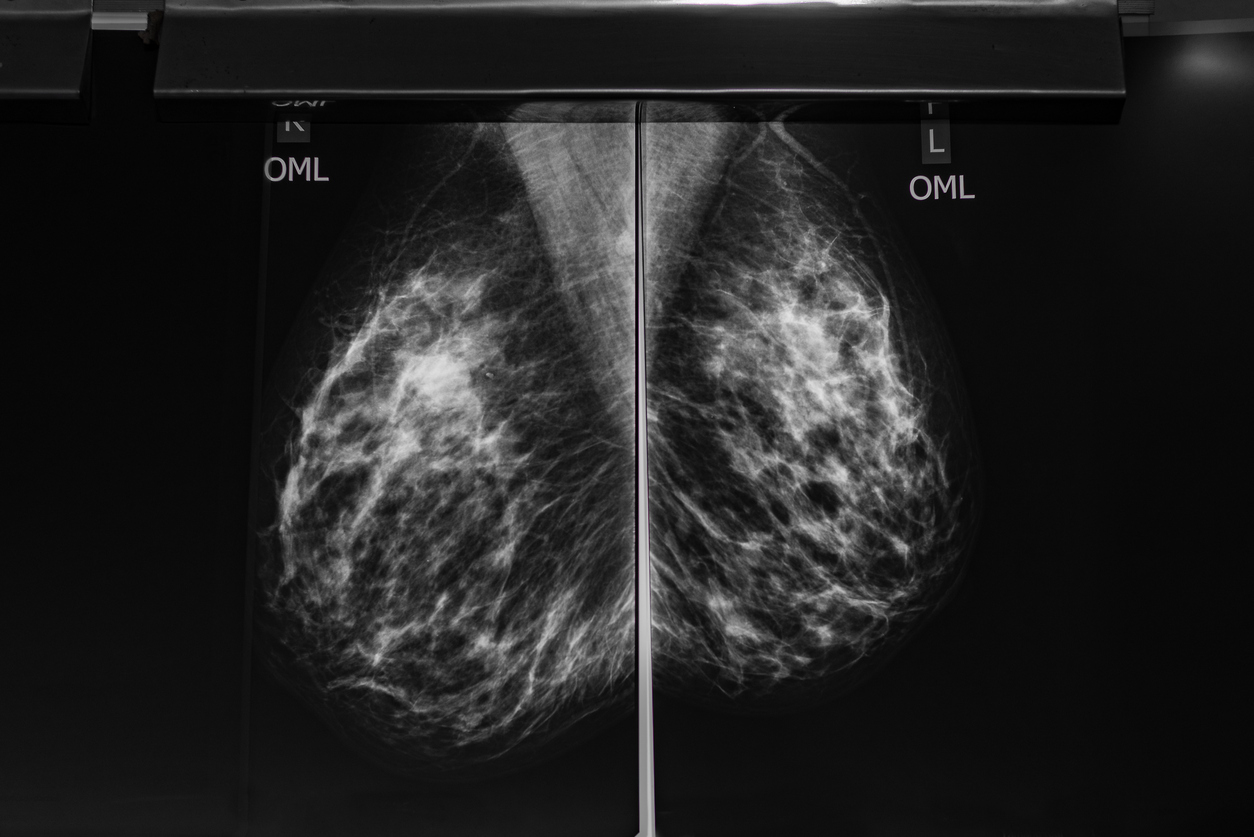

3D captures multiple slices of breast images, all at different angles. The images are brought together to create crystal-clear 3D reconstruction of the breast. The radiologist is then able to review the reconstruction, one thin slice at a time, almost like turning pages in a book. That makes it easier for doctors to see if there’s anything to be concerned about. And, there’s less chance for a cancer to hide behind overlapping tissue. If detected early, the five-year survival rate is 97%.

During the 3D mammography part of the exam, the X-ray arm sweeps in a slight arc over the breast, taking multiple breast images in just seconds. The radiologist is then able to view your breast tissue in one-millimeter layers. Instead of viewing all the complexities of your breast tissue in one flat image, the doctor can examine the tissue one page or “slice” at a time.

3D mammography (tomosynthesis) is a revolutionary, state-of-the-art screening and diagnostic tool designed for early breast cancer detection. During the 3D part of the exam, the X-ray arm sweeps in a slight arc over your breast, taking multiple breast images. Then, a computer produces a 3D image of your breast tissue in one-millimeter slices, providing greater visibility for the radiologist to see breast detail in a way never before possible. They can scroll through images of your entire breast like pages of a book. The 3D images make it possible for a radiologist to gain a better understanding of your breast tissue during screening and the confidence to reduce the need for follow-up imaging.

With conventional digital mammography, the radiologist views all the complexities of your breast tissue in one flat image. Sometimes breast tissue can overlap, giving the illusion of normal breast tissue looking like an abnormal area. By looking at the breast tissue in one-millimeter slices, the radiologist can provide a more confident assessment. In this way, 3D mammography finds cancers missed with conventional 2D mammography. It also means there is less chance your doctor will call you back later for a “second look,” because now they can see breast tissue more clearly.